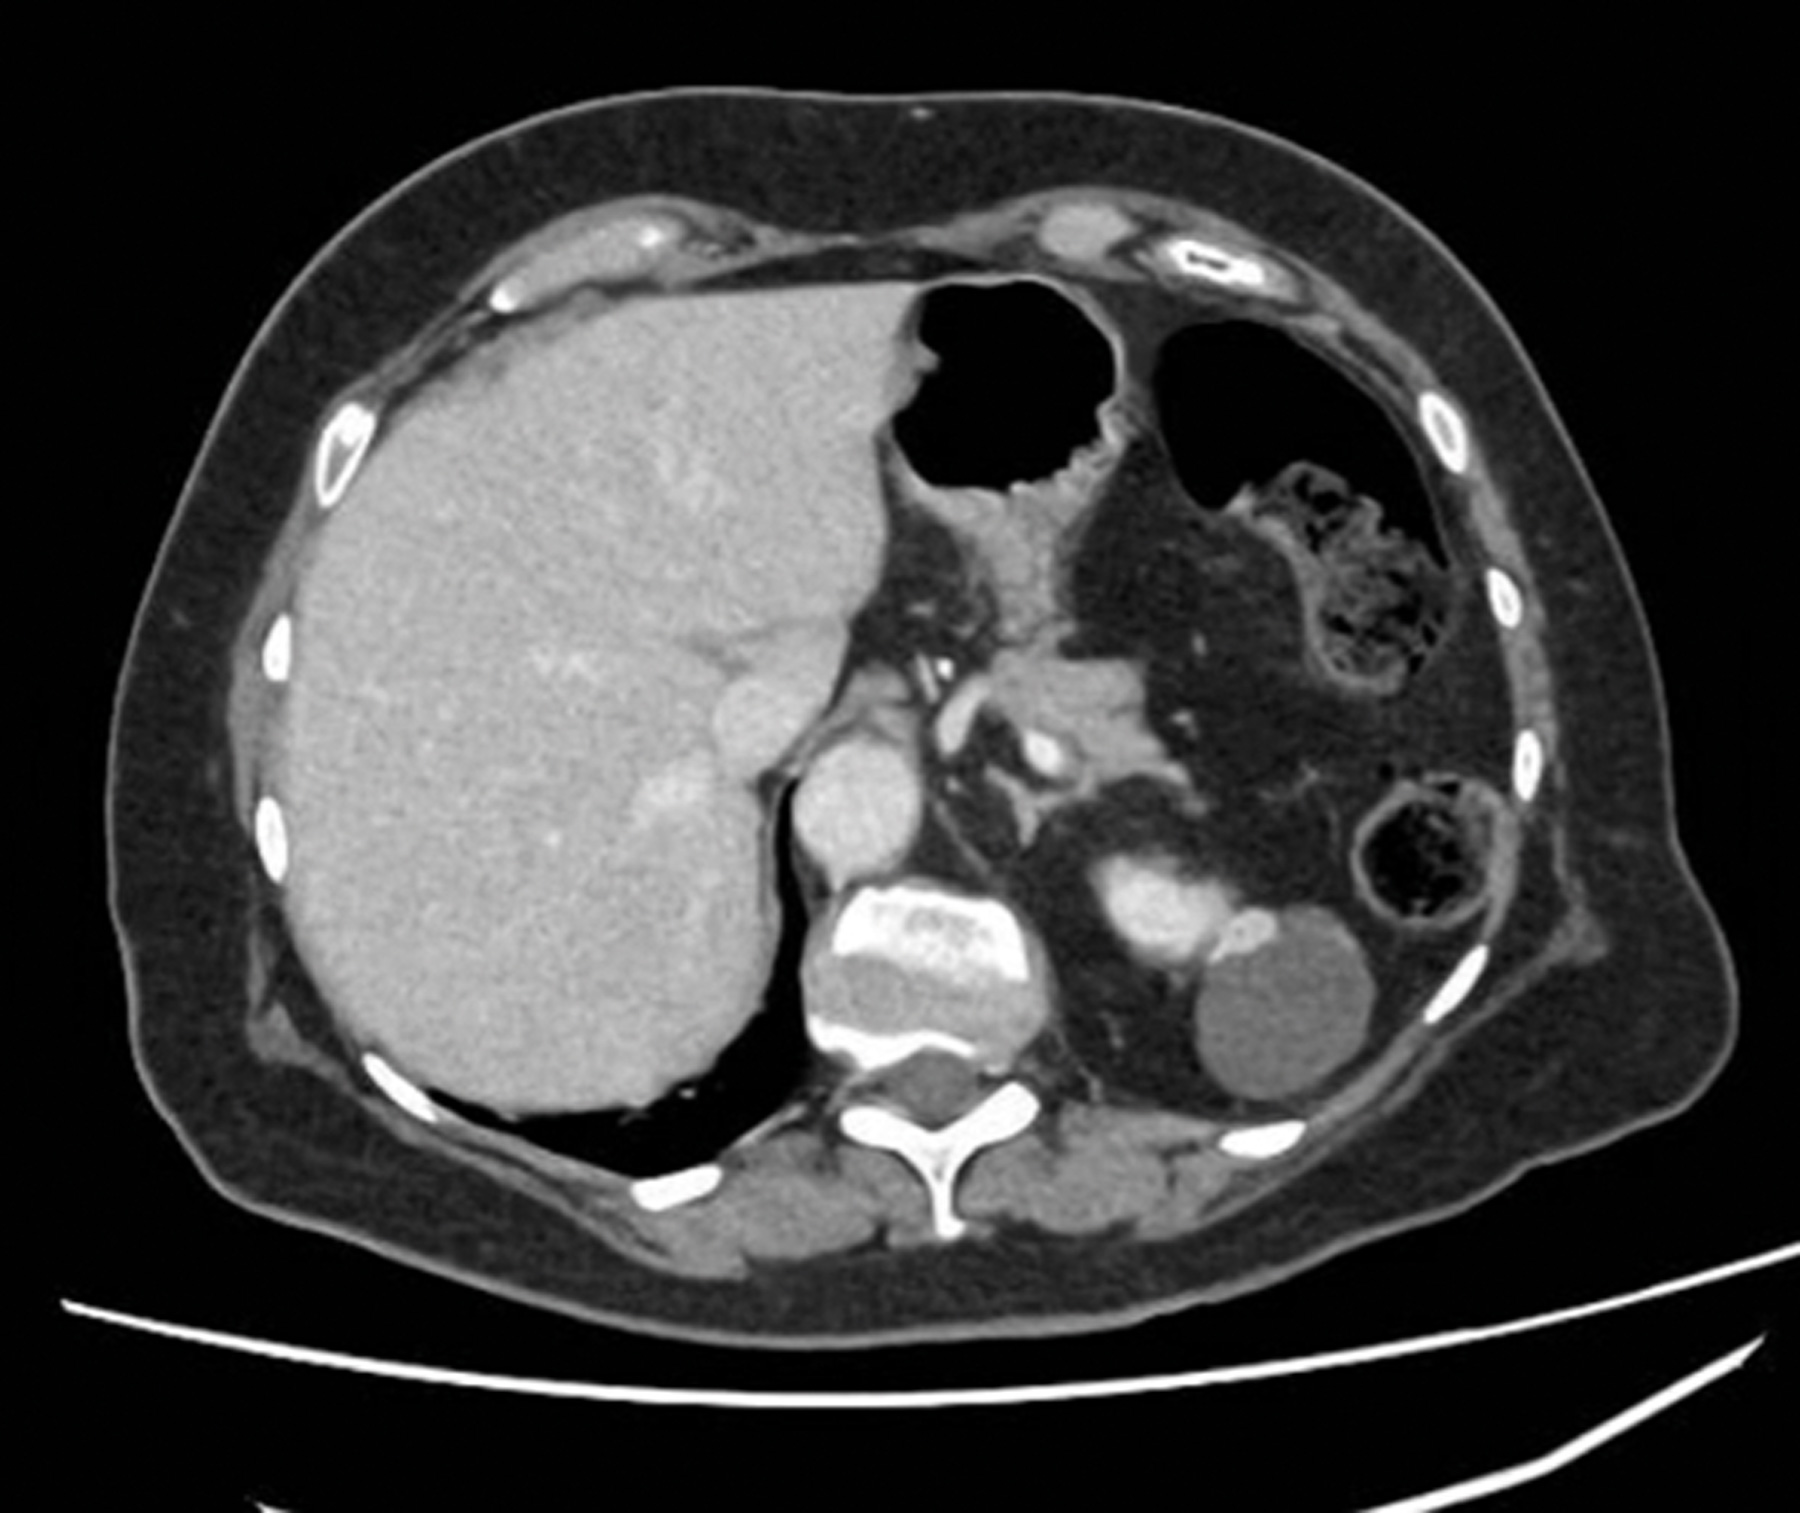

Case 2

A 65-year-old gentleman presented with visible haematuria and underwent the below CT scan. He has hypertension and hyperthyroidism.

Figure 2.

Figure 3.

- What do Figures 2 and 3 demonstrate? What is the stage of this lesion?

1. CT renal consists of multiple phases as outlined below [8]: Non-contrast phase - This is conducted prior to intravenous (IV) contrast administration, with the purpose of detecting calcifications (e.g., renal or ureteric stones) and identifying fat content in mass lesions (e.g., AML). It is also useful in having a baseline attenuation with which to compare the contrast images.Corticomedullary phase - This is conducted approximately 25-40 seconds after contrast injection. Its purpose is to highlight renal arteries, cortex and medulla (the renal cortex enhances preferentially). It is useful in assessing vascular anatomy which can aid surgical planning, and in demonstrating renal artery stenosis / arteriovenous malformations and other abnormalities. It can identify early enhancement in hypervascular tumours.Nephrogenic phase - This is conducted approximately 80-120 seconds after contrast injection. It allows both enhancement of the cortex and medulla and is the best phase for detecting renal masses.

2. This is a 5cm, exophytic, cystic, superior pole tumour of the left kidney, stage T1b N0 Mx.